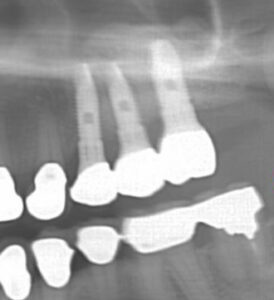

こんにちは。藤沢市の菅井歯科医院です。 今日は,骨の再生手術をしてインプラント治療を行った患者様の症例をご紹介します。 これは術前のCT画像です。上顎骨には上顎洞という空洞が存在しています。上の奥歯が無くなると,この空洞は大きくなっていく傾向にあります。この患者様も,1〜2mmほどの骨を残してあとは空洞になってしまっていました。 以前の歯科医師には,インプラントは不可能と言われていたそうです。 当院では,様々な骨の再生手術を行っております。 この患者様には,上顎洞の横から穴をあけて空洞の中に骨を造る,サイナスリフトという手術を行いました。半年後のCT画像です。 骨がなかった部位に骨が出来てい,CT上で白っぽく映っているのが分かります。 無事に骨が出来た部位にインプラントを3本埋入しました。 最終的にセラミックスの歯が入りました。 骨の再生治療を行うと治療期間は長く,費用も多くかかることがほとんどです。しかしながら,他院では不可能とされていた部位にインプラント治療を行えるというのはとても大きな魅力です。 自分でインプラントを諦めている方,他院では無理といわれた方,ぜひ一度当院にご相談ください。